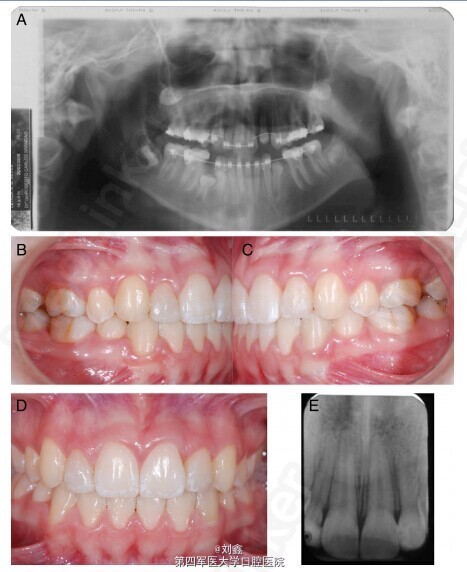

该患者为未成年女性,13 岁,因牙列不齐,影响美观要求正畸治疗。通过对患者的临床检查和曲面断层照片检查,发现患者上颌 15、22、25、35 牙齿尚未发育完全,12 牙齿发育过小;咬合关系和上下颌骨关系正常(图 1)。 根据患者的具体情况,制定详细的治疗计划。首先应用固定矫治器将 14 和 24 移向远中(图 2 A-D),13 随后萌出。21 和 23 之间的空间也被打开。依据 CT 三维影像确定移植位点牙齿的准确数据,考虑到 45 的大小、牙根的发育程度等情况,选择将 45 拔出后移植至 22 的位置。手术预备移植位点的牙槽窝 (图 2E,F)。 拔出 45,移植入预备好的 22 牙槽窝(图 3A-F)。缝合伤口,术后用树脂将 45 与邻牙固定两个月,四个月后开始移动 45(图 3G,H)。 该病例整个治疗过程持续 32 个月,治疗结束时临床和影像学检查显示,移植的前磨牙外形美观,牙根发育已完成,根管也已完全闭锁,预后良好(图 4A-E)。